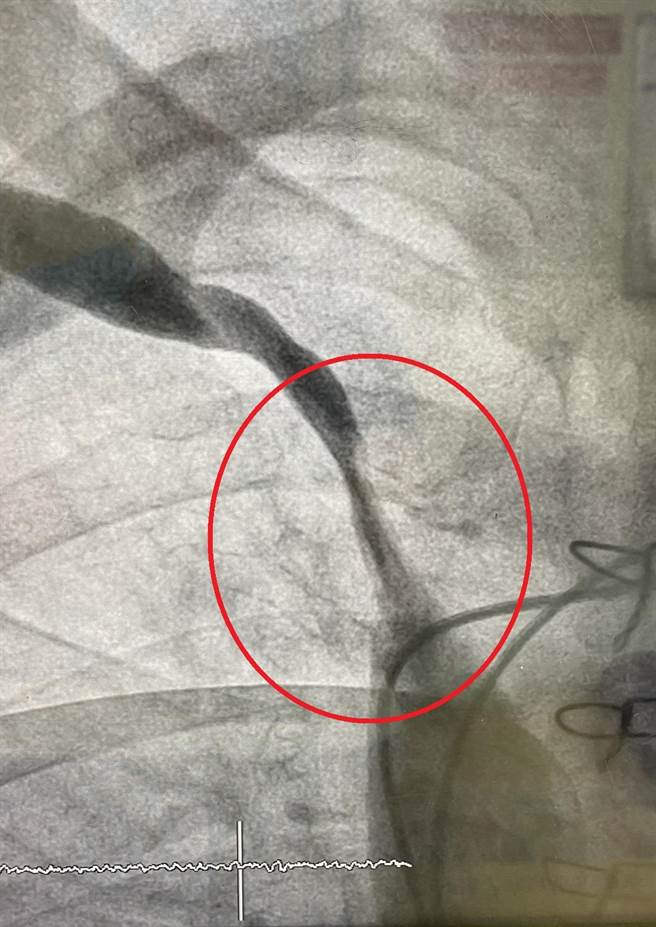

在接受中心静脉支架手术后,顺利解决让黄爷爷的血管恢復通畅(红圈处)。(大千医院提供/谢明俊苗栗传真)

80岁的黄爷爷是长期洗肾病人,2年前开始觉得洗肾时手臂会疼痛,医师安排血管摄影检查,发现他的中心静脉血管狭窄,经医师为他安排中心静脉支架手术,顺利解决黄爷爷血管狭窄的情形,让他不需再烦恼洗肾时疼痛的问题了!

医师指出,一般的治疗以导管球囊扩张为主,但如果狭窄状况严重,导致球囊扩张效果不好,则可以选择置放支架治疗。过去苗栗县的洗肾病人如需接受支架治疗,都必须奔波外县市,大千引进此项技术后,对洗肾病人是一大福音。